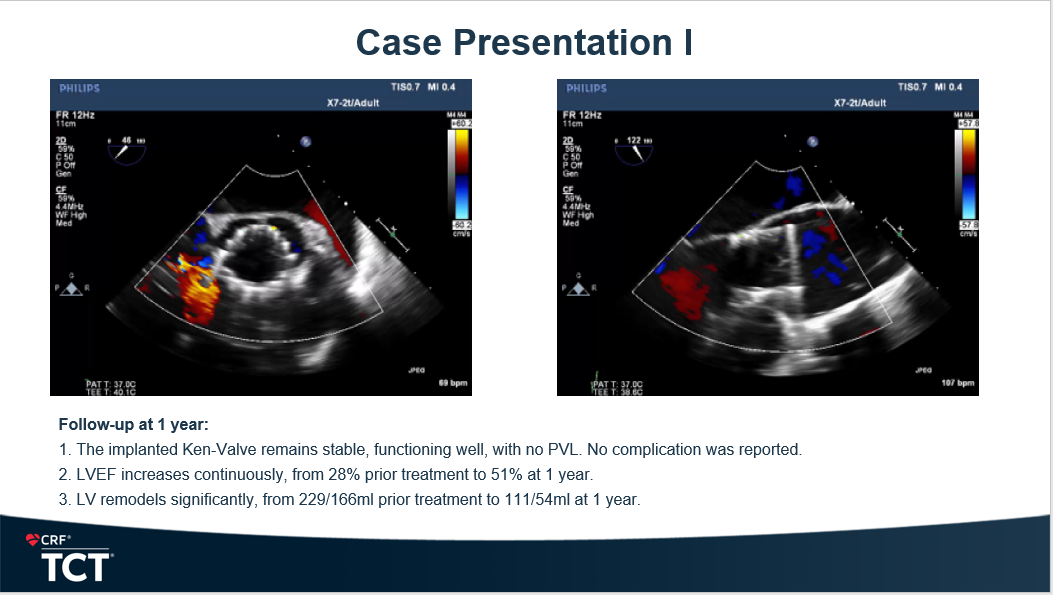

在此基础上,Anson Cheung教授进一步分享了两例具有代表性的Ken-Valve临床病例。第一例为一名68岁的重度主动脉瓣反流患者,术前左心室显著扩张,射血分数仅28%;手术团队在硬导丝引导下推进输送系统,并通过适度调整系统弯曲角度,以获得理想同轴度后精准释放Ken-Valve瓣膜,术后瓣膜功能良好、无瓣周漏。随访1年时,患者LVEF恢复至51%,左心室重构明显改善,NYHA分级由Ⅲ级提升至Ⅰ级。